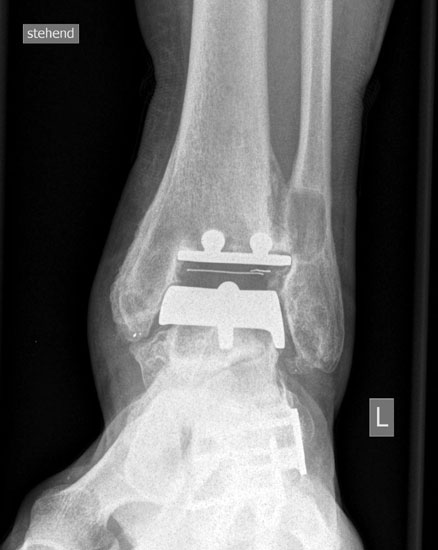

• Prothesenplanung anhand von Röntgenschablonen (Abb. 1 und 2).

• Röntgenkontrollen: 2 Tage postoperativ, 6 Wochen postoperativ; 3, 6, 12 Monate postoperativ, dann im Abstand von 12-18 Monaten.